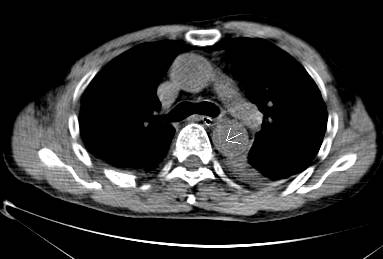

病例二

胸部平扫CT提示升主动脉增宽(红色星形标记),CTA证实A型主动脉夹层伴升主动脉夹层动脉瘤形成。